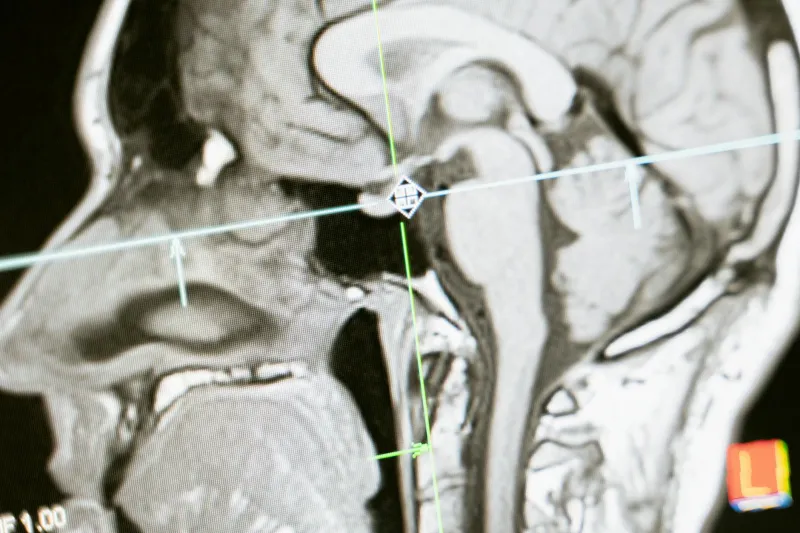

Modern neuroimaging technology, particularly functional MRI (fMRI), allows researchers to observe brain activity in real time as people perform various tasks. What those scans consistently reveal is that almost no cognitive task activates just one hemisphere. Reading, solving math problems, listening to music, making decisions, experiencing emotions — all of these activities light up regions across both hemispheres simultaneously.

A large-scale study published in 2013 by researchers at the University of Utah examined brain scans from more than 1,000 people and specifically looked for evidence that individuals showed a consistent dominance of one hemisphere over the other. They found no such pattern. People did not cluster into left-brain dominant and right-brain dominant groups. Both hemispheres were used roughly equally across the sample, and there was no evidence that someone who used their left hemisphere more for one task would consistently use it more for other tasks.